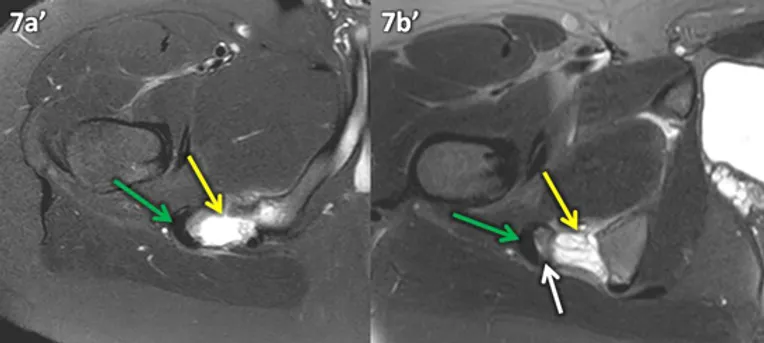

Figura 7 (a-b): Imagens de RM do quadril direito na ponderação T2 com supressão de gordura nos planos transversal (7a) e transversal oblíquo (7b).

Figura 7 (a-b)’: Imagens de RM do quadril direito na ponderação T2 com supressão de gordura nos planos transversal (7a’) e transversal oblíquo (7b’) mostrando o fragmento avulsionado (seta branca na figura 7b’) onde se originam os tendões isquiotibiais (setas verdes), com maior afastamento e quantidade de líquido (setas amarelas) entre o fragmento e o ísquio.